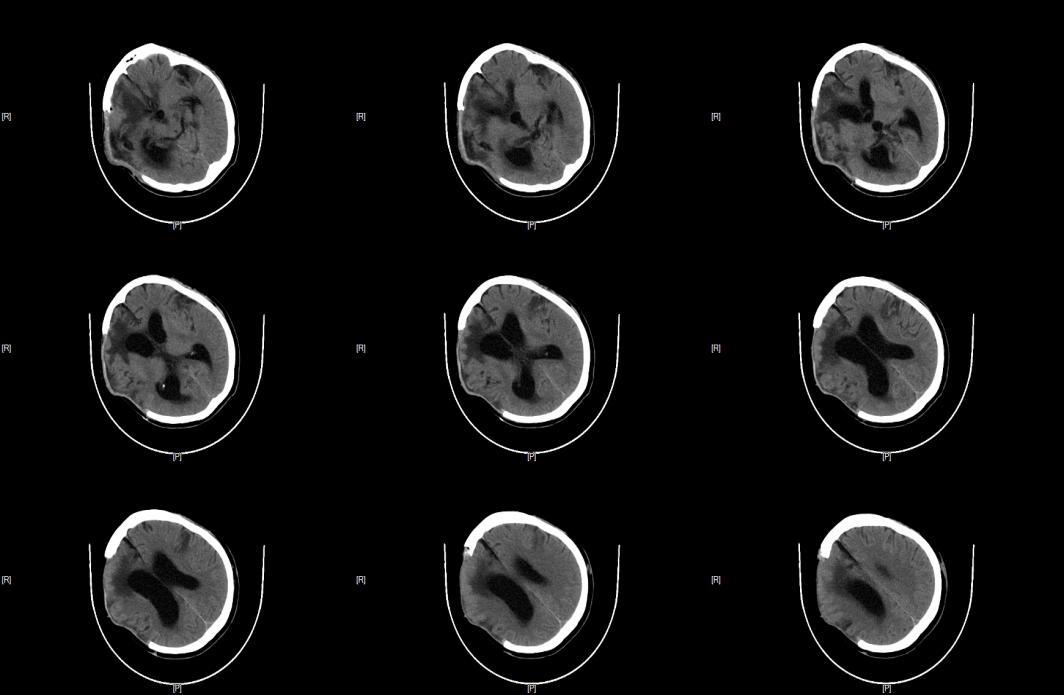

查CT提示:左顶部皮下血肿,右额顶颞部、左额颞部硬膜下血肿(SAH);两肺条片影,两侧胸膜反应,左侧多发肋骨骨折。

急诊以“全身多发伤”收入神经外科,经过神经外科团队的全力抢救,急诊行开颅血肿清除+去骨瓣减压术,术后以对症治疗6周,患者生命体征逐渐平稳,但患者的意识水平未见改善,持续昏迷。

图片

▲SCS(脊髓电刺激)术前,复查头颅CT:血肿已吸收